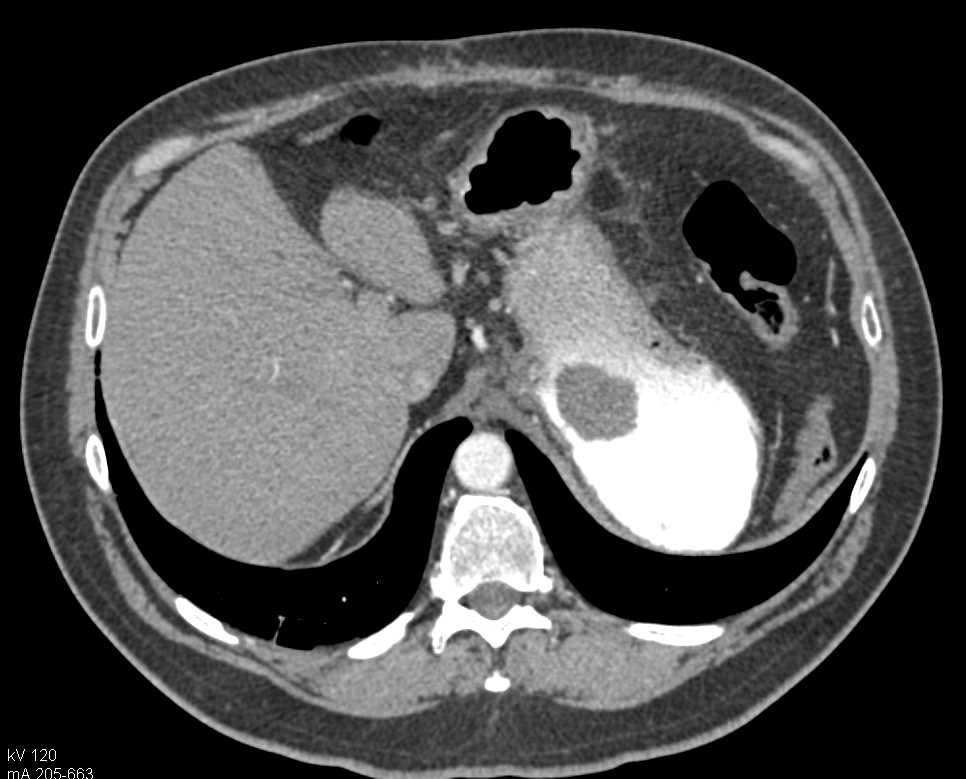

Infiltrating Gastric Adenocarcinoma